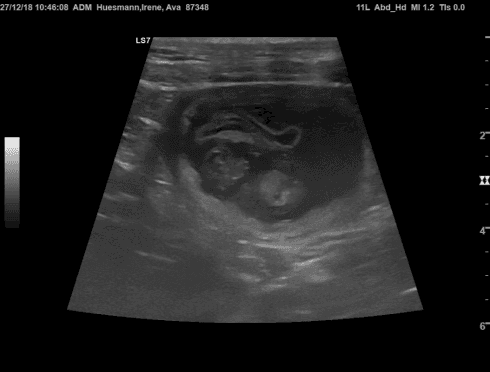

Nun ist das Geheimnis gelüftet! Auf dem Ultraschall waren viele kleine Blasen zu sehen! Ava und Nanuk bekommen Ende Januar Welpen!!!

Ich freue mich sehr und bin gespannt auf die kleinen Mäuse!! Herzlichen Glückwunsch Irene Huesmann und eine gute, restliche Trächtigkeit für Ava!